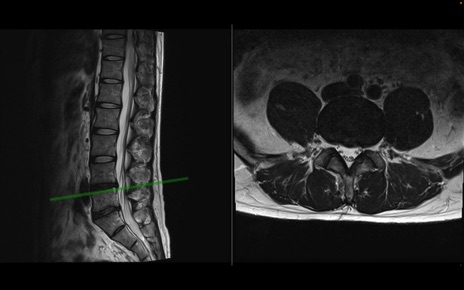

【症例】40歳代男性

【主訴】左臀部〜大腿後面痛み

【現病歴】2週間前から腰痛あり。2日前に夜中にくしゃみをした際に激痛が出現。疼痛強いため来院。

【身体所見】左臀部〜大腿後面、下腿後面のしびれ。SLR -/+ 30度、うつ伏せ困難、筋力低下なし。

異常所見と診断は?